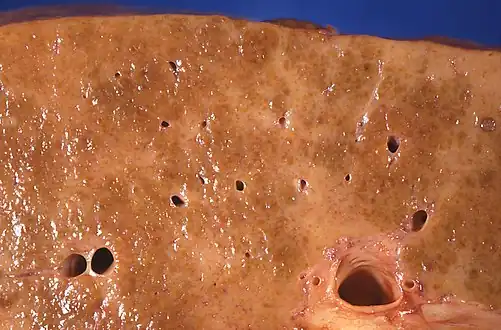

| Cross-section of human liver with cirrhosis | |

Macroscopically, the liver is initially enlarged, but with the progression of the disease, it becomes smaller. Its surface is irregular, the consistency is firm, and if associated with steatosis the color is yellow. Depending on the size of the nodules, there are three macroscopic types: micronodular, macronodular, and mixed cirrhosis. In the micronodular form (Laennec's cirrhosis or portal cirrhosis), regenerating nodules are under 3 mm. In macronodular cirrhosis (post-necrotic cirrhosis), the nodules are larger than 3 mm. Mixed cirrhosis consists of nodules of different sizes.[85]

Micronodular cirrhosis, with diffuse areas of pallor

Micronodular cirrhosis, with diffuse areas of pallor.jpg.webp) Pale macronodules of cirrhosis